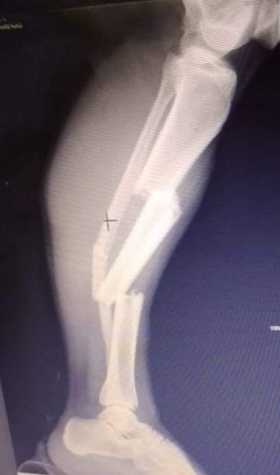

Yeimi Lorena Cardona Arenas, con fractura en tibia y peroné de la pierna derecha. Trasladada a Manizales.